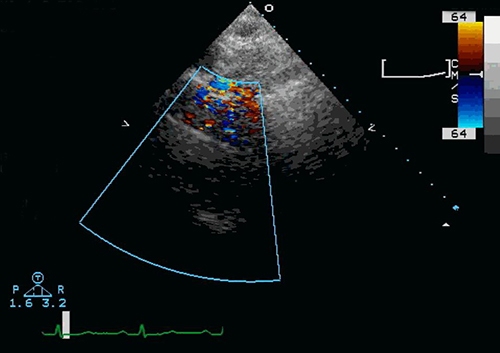

L’échocardiographie transthoracique (ETT), ou échocardiographie, est une technique d’imagerie qui repose sur l’utilisation d’ultrasons (ondes acoustiques de haute fréquence) pour produire des images du cœur. Cet examen diagnostique permet au médecin de visualiser le cœur et son irrigation, d’évaluer le volume du cœur, sa capacité à se contracter ainsi que le fonctionnement des valvules.

Une sonde échographique que l’on place sur la poitrine (thorax) du patient émet des ultrasons pour produire des images du cœur. On utilise parfois le système Doppler pour analyser la vitesse et la direction du flux sanguin. Les images, visibles sur un moniteur, sont enregistrées numériquement.